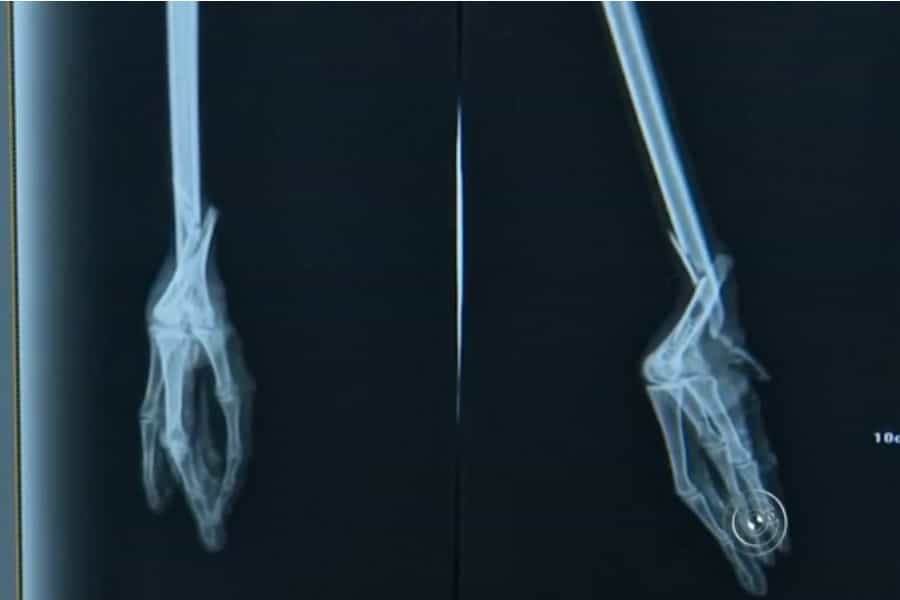

Luego de la lesión, el ave quedó con pocas posibilidades de sobrevivir, por eso los veterinarios optaron por implantarle una pata ortopédica de carbono que medía 18 centímetros, que fue donada por un fabricante de prótesis.